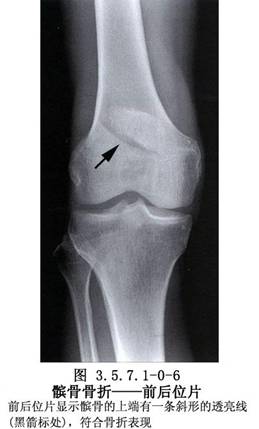

髌骨的解剖及髌骨骨折影像表现见下图(图3.5.7.1-0-1~3.5.7.1-0-10)。